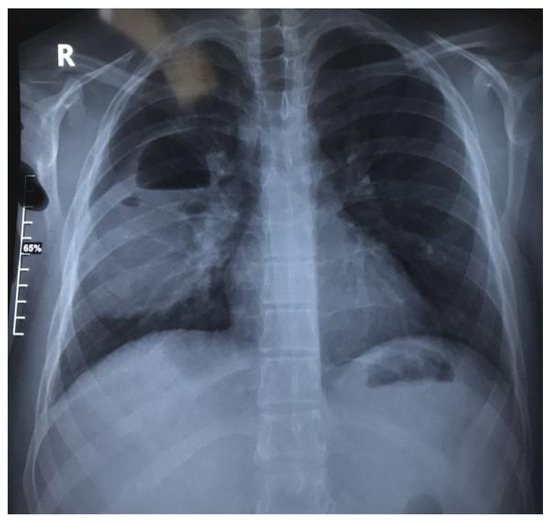

1.9.1. Case 1